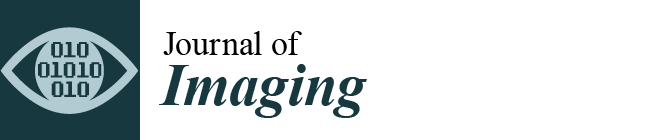

2.3. Preoperative Radiographic Assessment

2.4. Postoperative Radiographic Assessment